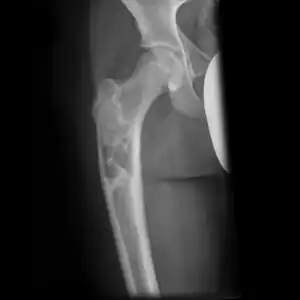

Multloculated cavity in the long bone of the thigh, near the hip.

Break through simple bone cyst in the long bone of the thigh, near the hip.